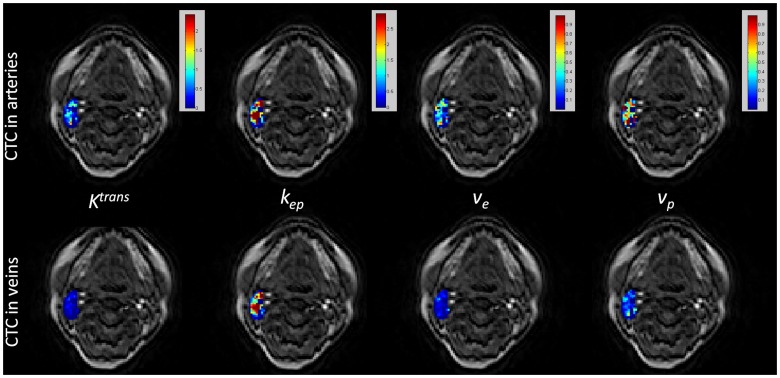

For voxel-wise fitting within the lesion ROIs, around 7–24% of total voxels for different subjects failed of fitting due to the violation of fitting restrictions or the poor goodness of fit when arterial CTCs were used, while the corresponding voxel fraction was reduced to 3–15% by using venous CTCs. The successfully fitted pixels had the average goodness of fit R2 of 0.84 and 0.89 for all lesions by using arterial and venous CTCs, respectively. These results indicated that the Tofts model fitting by using venous CTCs was more robust and less vulnerable to the noise and signal fluctuations. Representative Tofts parameter maps within a metastatic node ROI (overlaid on the first time point pre-contrast DCE image) by using the slice-averaged dynamic CTCs in arteries and veins were illustrated in Fig. 5.

Figure 5. Kinetic Parameter Maps within a Metastatic Node.

The kinetic parameter maps (goodness of fit R2> = 0.8) within a metastatic node overlaid on the first time point DCE image by using the slice-averaged CTCs in arteries (first row) and veins (second row).